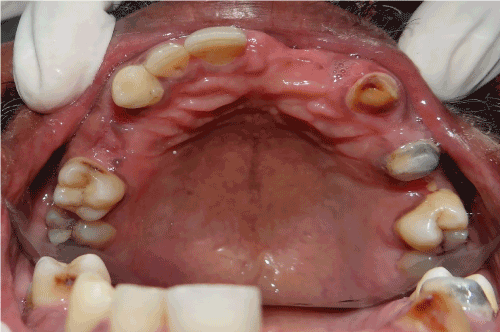

A 56-year-old male patient reported the Department of Prosthodontics at SRM Dental College and Hospital, Ramapuram, Chennai, India with a chief complaint of fractured fixed partial denture in the upper right teeth region and he wants to restore the teeth. On clinical examination, it was found that 11, 12, 14, 16, 24 and 25 are missing in maxillary arch and 36, 44, 45 and 46 are missing in mandibular arch. The teeth preparation had been done previously in 13, 15 and was periodontally sound. Due to the financial and economic reasons of the patient, tooth supported removable partial denture has been given as a alternative treatment option to fixed partial denture using the existing prepared tooth as abutment.

Figure 1. Intra oral view –maxilla